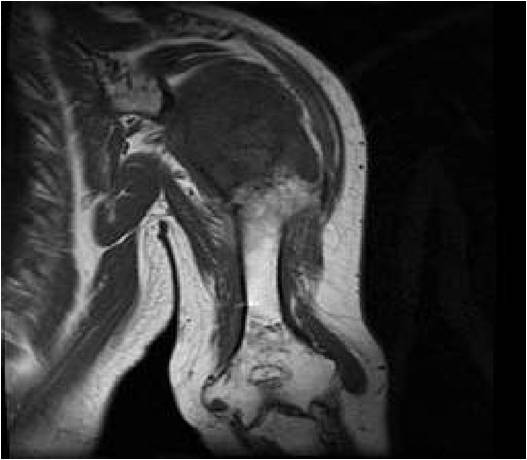

MRI:

- Lobulated margin (Lobular Growth Pattern)

- T1 Weighted Images: Intermediate Signal Intensity

- Calcifications will be low signal

- T2 Weighted Images: High Signal Intensity

- High water content shows as high signal on T2 weighted images

- Marked increased intensity long TR images

- Calcified chondroid – low intensity all sequences

- There should never be any cortical destruction nor a soft tissue component. If this exists then the tumor must be a chondrosarcoma.

- Endosteal scalloping and cortical expansion is acceptable for phalangeal tumors. In most benign long bone cartilage tumors there is minimal endosteal scalloping but there should be no cortical expansion nor thickening. There should be no cortical destruction and no soft tissue component associated with an enchondroma. Cortical destruction, periosteal thickening, cortical expansion and a soft tissue component indicates a chondrosarcoma of the long bone.